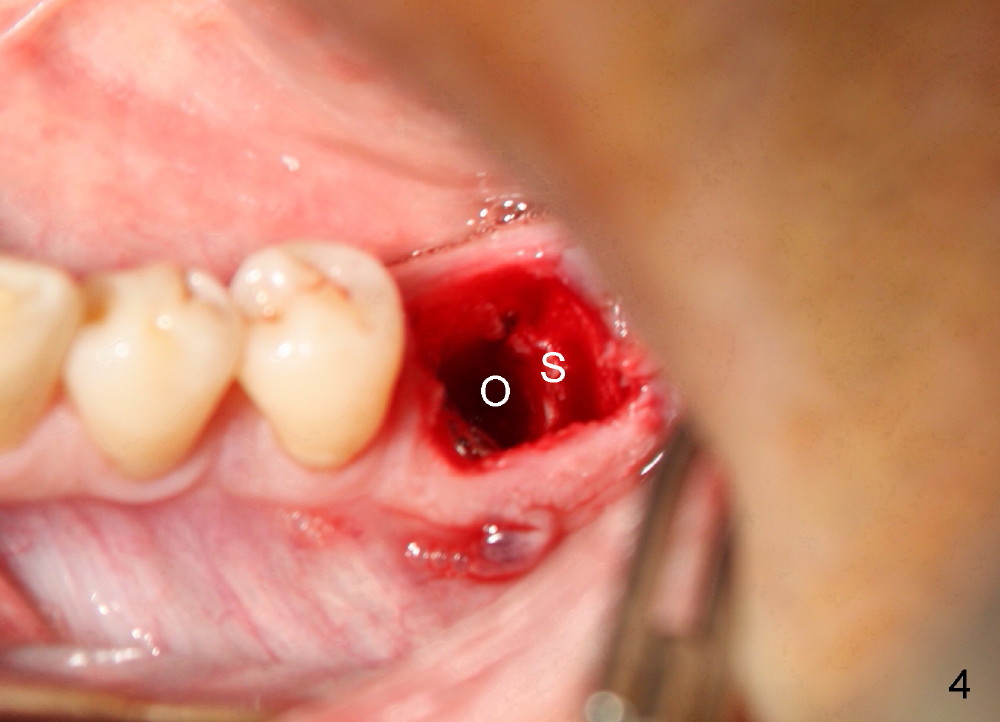

A 41-year-old man has discomfort in the lower left 1st molar. Exam shows swelling and a fistula in the mesiobuccal gingiva (Fig.1 >) and large radiolucency around the mesial root (Fig.2 *). After extraction and thorough debridement, osteotomy is initiated in the mesial socket, but the upper portion of the reamer (Fig.3 R, 2.5 mm) is placed in the middle of the edentulous space. By the time 5 mm reamer is removed, the osteotomy (Fig.4 O) forms mainly in the mesial socket with the septum (S) deviated to the distal socket. A 7x17 mm tap is placed with stability (Fig.5 T). An implant with the same dimension is placed with insertion torque more than 60 Ncm (Fig.6 I). With the large implant, two proximal sutures are able to close the remaining socket gaps (Fig.7). The swelling and fistula disappears and the gingiva tightly surrounds the implant in 1 week postop (Fig.8).